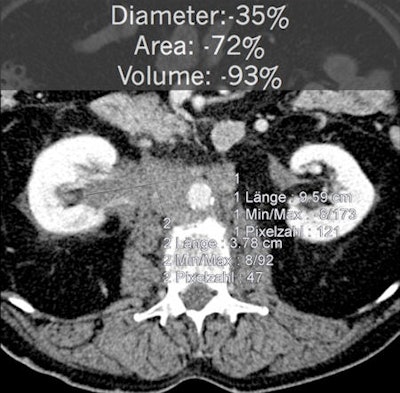

As shown in these cases, volumetry is more sensitive than RECIST measurements for determining therapy treatment response. All images courtesy of Dr. Anno Graser.

In patient data from the CRYSTAL metastatic colorectal treatment trial, RECIST measurements showed early tumor shrinkage of 15.4%. But volumetry revealed early tumor shrinkage of 61.5%, Graser said.